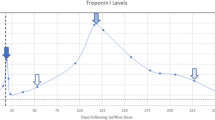

A male patient with non-consanguineous parents was healthy until the age of 4 years when he started to develop episodes of fever and chest discomfort. At the initial presentation, electrocardiography (ECG) showed sinus tachycardia with T-wave inversions and his C-reactive protein (CRP) was elevated (57 mg/L). He was concluded to suffer from mild myocarditis from which he recovered well. At the age of 5 years, he experienced another episode of chest pain and sinus tachycardia with T-wave inversions. CRP (58 mg/L) and troponin I (TnI) (2.1 ng/mL; normal < 0.03 ng/mL) were elevated. Following these first episodes, his growth, physical abilities, and developmental path continued to progress despite the recurrent myocarditis episodes. He received a diagnosis of allergic asthma and underwent treatment for it at the age of 9. He continued to suffer recurrent febrile episodes accompanied by chest pain, tachycardia, an elevated troponin T (TnT) and T-wave inversions in his ECG. Representative ECG findings consistent with myocarditis episode (TnT 485 ng/L, normal < 50 mg/L) at the age of 17 years are shown in Fig. 1A. During that episode, echocardiography showed a mild and transient reduction in left ventricular function. Myocardial magnetic resonance imaging (MRI) (Fig. 1B) demonstrated edema and enhancement consistent with myocarditis. Cardiac muscle antibodies were negative, and no evidence of respiratory infection pathogens was found (Supplemental Methods). The patient did not develop clinical or laboratory findings suggestive of HLH [18] Histological staining of myocardial biopsies collected from four locations were positive for CD3+ T cells (14/mm2) and macrophages consistent with myocarditis [9]. The myocardial biopsy was negative for TIM-3 expression (Fig. 1C). Beginning at the age of 17 years, febrile myocarditis episodes were treated with anakinra, an IL-1β receptor antagonist (Kineret®, 100 mg daily, 4 to 7 days), with a good clinical response. Due to successful anakinra response, the patient has not required hospitalization. Despite the tonsillectomy due to episodes of tonsillitis, he has not encountered additional health concerns.

(A) Representative electrocardiographs (ECG, 50 mm/s) on days 1 to 5 of hospitalization during an episode of acute myocarditis at age 17 years (B) Late gadolinium enhancement pattern (arrows) consistent with myocarditis in cardiac MRI (C) Representative images of TIM-3 immunostaining in myocardium biopsies. TIM-3 staining was positive (red arrows) in the control and negative in the patient’s samples